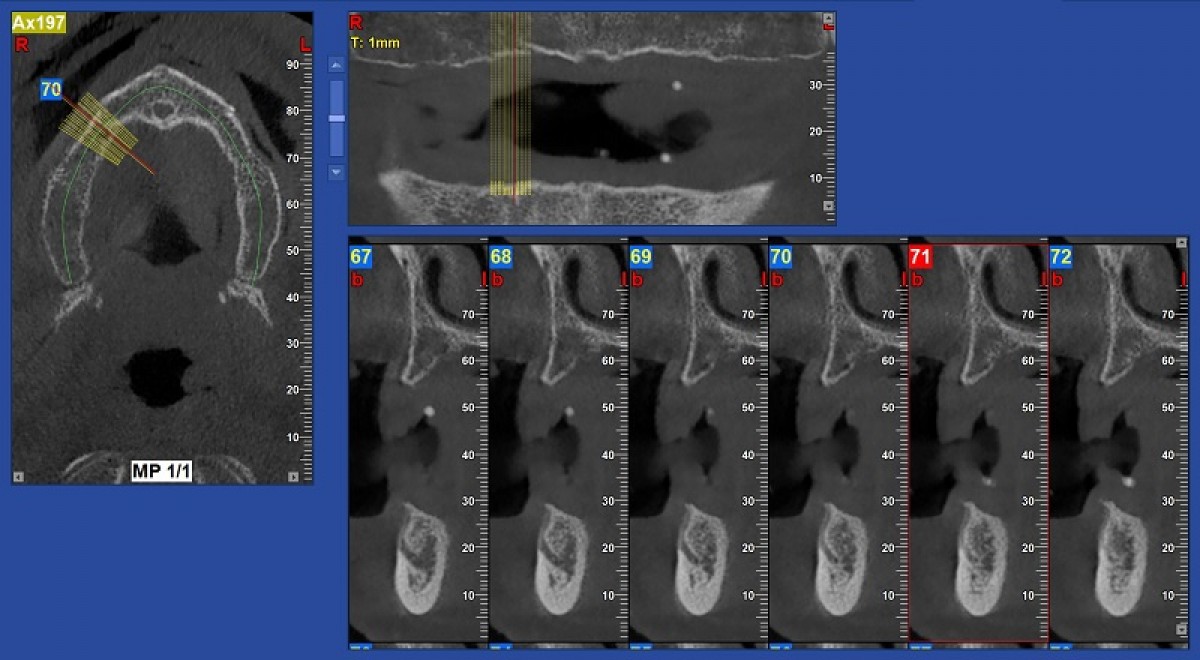

In this particular case, the computerized cephalometric analysis performed using the Nemoceph (Nemotec) software, highlighted on the lateral projection a skeletal class 1, a brachyfacial type and pathological positioning of the upper and lower incisors; the latter appeared retro-positioned compared to their respective skeletal bases (incisive overbite) and linguo-inclined (insufficient torque). This situation gave rise to the so-called "incisor wall" which could compromise correct occlusal contact and proper functioning of the temporomandibular joints. It also influences the aesthetics of the smile. Cephalometric analysis on the frontal plane showed a good transverse relationship between the upper and lower jaws and confirmed the rightward deviation of the lower midline. To plan the orthodontic treatment, we performed a cephalometric VTO to simulate the correct positions that the incisors should reach at the end of the course of treatment (fig. 5).

The cephalometric VTO allowed us to identify the exact movements the incisors need to make in the sagittal and vertical planes. To complete the three-dimensional treatment planning, the virtual set-up was used. The dental arches were further scanned using the Trios (3Shape) scanner (fig. 6).

The intraoral scan file was then uploaded to the Insigna (Ormco) web application where the arches were segmented (i.e. the teeth were separated from each other) and an initial virtual set-up was performed by Insigna technicians. Subsequently - again on the Insigna web application - we perfected and completed the virtual set-up. The settings for the position and the angle of the upper and lower incisors were based on the cephalometric VTO values (fig. 7).